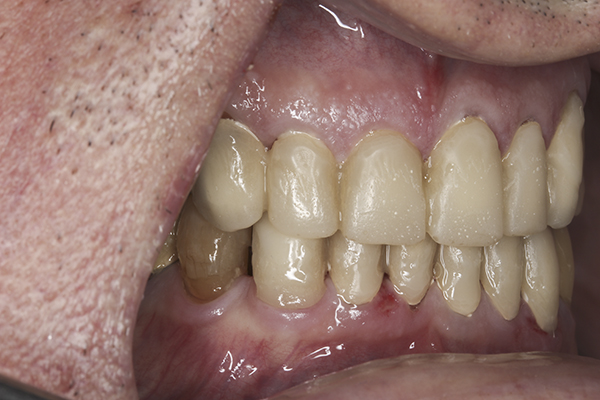

(35.) Postoperative right lateral, closed view.

Figure 35

(36.) Postoperative anterior, closed view. Note the position of the upper and lower canines to provide canine guidance.

Figure 36

(37.) Postoperative left lateral, closed view.

Figure 37